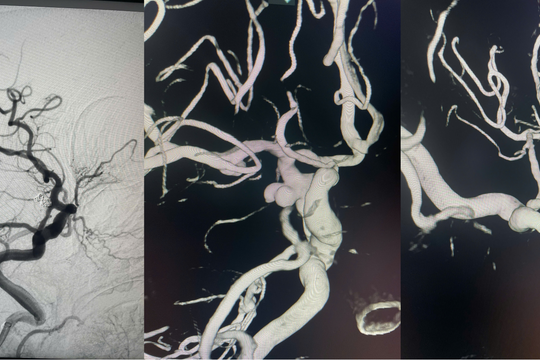

Bệnh viện Đa khoa Quảng Nam can thiệp thành công ca xuất huyết dưới nhện do vỡ túi phình động mạch não phức tạp

ĐNO - Tin từ Bệnh viện Đa khoa Quảng Nam ngày 10/1 cho biết, bệnh viện vừa can thiệp thành công một trường hợp xuất huyết dưới nhện do vỡ túi phình động mạch não, một bệnh lý cấp cứu thần kinh đặc biệt nguy hiểm, có nguy cơ tử vong rất cao nếu không được xử trí kịp thời.